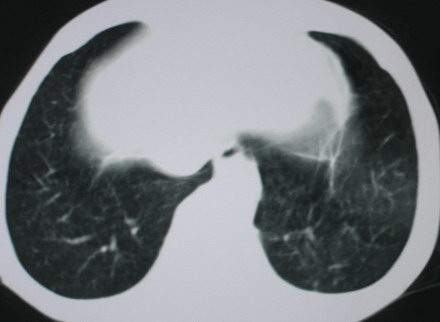

以下是引用医影拾贝在2008-6-3 18:48:00的发言:[br]双上肺弥漫性小结节影,纵隔窗内钙化淋巴结影,考虑血播性tb可能性较大,不除外肺ca可能

以下是引用卜一在2008-6-3 19:33:00的发言:[br]双肺结节,以双上肺分布为多,期间搀杂片状致密影及索条致密影。考虑:继发性肺结核伴血型播散可能性大。不除外肺泡ca的可能!另:椎体退变!

以下是引用panyishengct在2008-6-3 21:09:00的发言:[br]双上肺弥漫性小结节影,纵隔窗内钙化淋巴结影,考虑矽肺或/和tb可能性较大,不除外肺ca可能。腰椎考虑退变。 [br][br]